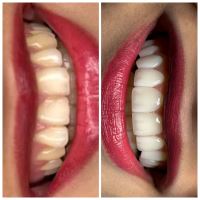

لمینت سرامیکی E.MAX تکنیک لیرینگ

لمینت لیرینگ دندان یک روش جدیدی است که در آن با توجه به شکل و فرم دندان های زیباجو، شیارهایی بر روی لمینت دندان ایجاد می کنند. که همین شیارها موجب می شوند تا ظاهر لمینت های دندان، بسیار طبیعی تر و زیباتر شود. همه ی مراحل لیرینگ لمینت دندان به روش لیرینگ در لابراتور پردازش و ساخته و سپس توسط دندانپزشک نصب می شوند.

تفاوت لمینت لیرینگ با لمینت معمولی:

باید بگوییم که در روش لمینت لیرینگ در مقایسه با لمینت دندان معمولی، ظاهر دندان ها بسیار طبیعی تر و زیباتر شده و جلوه بیش تری دارند.

موارد استفاده از لمینت دندان به روش لیرینگ

| اصلاح رنگ و فرم دندانها: اگر دندانهای شما لکهدار، زرد، نامرتب، کوتاه، بلند، شکسته یا نامنظم هستند، لمینت لیرینگ میتواند به طور کامل این نواقص را برطرف کرده و ظاهری زیبا و متقارن به آنها ببخشد. |

| بستن فضاهای بین دندانی: اگر بین دندانهای شما فضاهای خالی وجود دارد، لمینت لیرینگ میتواند این فضاها را به طور کامل پر کرده و ظاهری یکدست و زیبا به لبخند شما بدهد. |